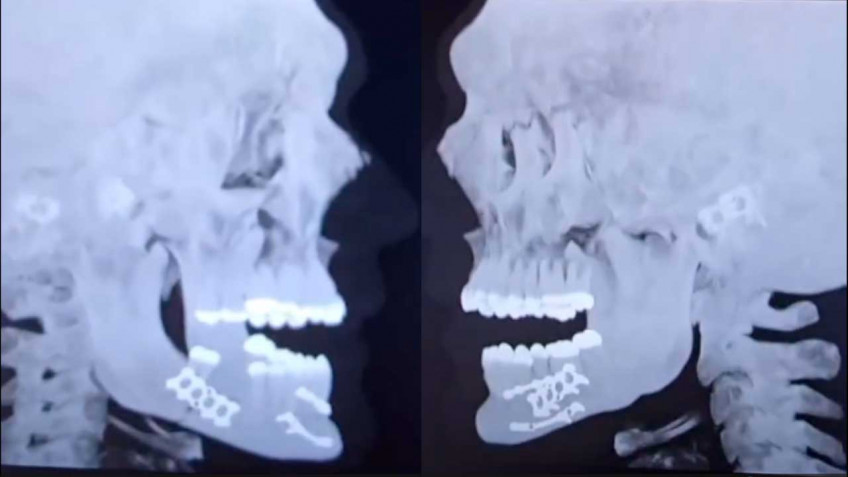

Джейку Полу удалили зубы и установили титановые пластины на сломанную челюсть

Джейк Пол, проигравший сегодня утром экс-чемпиону мира в супертяжелом весе Энтони Джошуа, рассказал об операции, которую ему пришлось сделать в связи с полученным в ходе поединка переломом челюсти.

«Операция прошла хорошо, спасибо всем за поддержку, — написал Пол в соцсети. — Две титановые пластины с каждой стороны. Удалили несколько зубов. Только жидкая пища в течение семи дней».